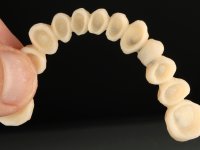

Foi proposto ao paciente fazer uma reabilitação total com infraestruturas em zircónia revestidas a cerâmica. No maxilar superior, seriam realizadas 6 coroas (1.3/1.2/1.1/2.1/2.2/2.3), uma ponte de 3 elementos (1.4/1.5/1.6) e uma ponte de 4 elementos (2.4/2.5/2.6 e 2.7). No maxilar inferior, foram propostas 7 coroas (4.3/4.2/4.1/3.1/3.2/3.5 /3.6) e duas pontes (4.4//4.5/4.6) e (3.3/3.4#/3.4).O objetivo seria subir a D.V.O., descruzar a mordida do lado direito, eliminar as infiltrações e as exposições radiculares e reabilitar o paciente com estruturas protéticas com aspeto mais natural.

Avaliada a situação inicial em conjunto com o médico dentista, foi considerado prioritário alterar a forma dos dentes, subir 1.5mm a D.V.O. e descruzar a mordida do 1º Quadrante. Na confeção da ponte provisória superior de acrílico com reforço metálico foram já ensaiadas essas alterações. Optamos por um monobloco de 13 dentes com o intuito de manter a estabilidade posicional dos dentes re- preparados. Após remoção das coroas e pontes antigas foi feita a re-preparação dentária. A ponte provisória foi rebasada em boca, primeiro com acrílico auto-polimerizável e depois com resina composta. Após 4 semanas de integração da ponte provisória superior foi confecionada a ponte provisória inferior, corrigindo-se finalmente as discrepâncias existentes no plano oclusal. As impressões foram realizadas com a técnica de dupla mistura, com dupla mistura. Simultaneamente foram feitos os registos da relação inter-maxilar e da relação do maxilar superior com a base do crânio, utilizando o arco facial. Montados os modelos de trabalho em articulador semi-ajustável, foram confecionadas as peças próteticas, utilizando tecnologia CAD-CAM para a realização das infra-estruturas em zircónia. A colocação da cerâmica foi feita procurando que a forma dos dentes reproduzisse uma forma anatómica natural. A tonalidade foi condicionada pela vontade do paciente. Foi feita uma prova com a cerâmica em “biscuit” para verificação técnica e validação estética. Após aprovação pelo paciente o trabalho foi finalizado e colocado em boca.